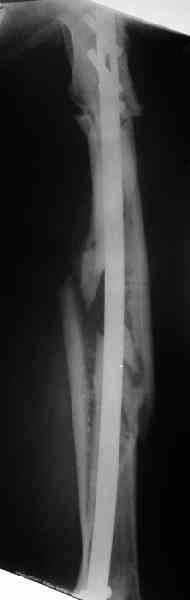

Уважаемые коллеги! Пришел на консультацию вот такой больной (первые 3-и рисунка). Травма автодорожная, апрель 2006г. Лечился консервативно, вытяжение и гипс. Через пять месяцев стал ходить. Укорочение бедра 6 см. 26 февраля 2007г. оступился, упал. Прооперирован в г.Баку - наложен стержневой аппарат. Ходит с костылями, наступая на левую ногу. Мы попросили что нибудь из ранних снимков. Принес рентгенограммы перелома (рис. 4,5). Посмотрели, наснимали сами (рис. 6-10). Похоже, что нет сращения нигде. Хотелось - бы обсудить следующие вопросы:1. дальнейшая тактика - реостеосинтез или подождать (ослабить аппарат, дать нагрузку и т.д.)?2. если реостеосинтез - то чем и как? Юрий Алексеевич Булахтин